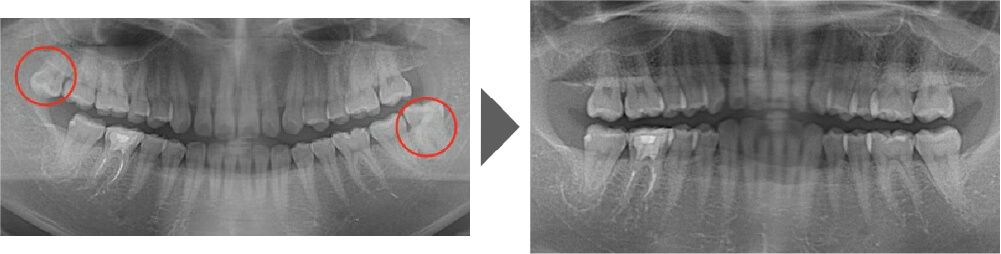

抜歯症例③

ご覧いただいた通り、生えている向きが真横に近い状態で、 通常は時間を要する抜歯です。

【抜歯所要予約時間】

15分

(麻酔の時間があるので処置自体はもっと短いです)